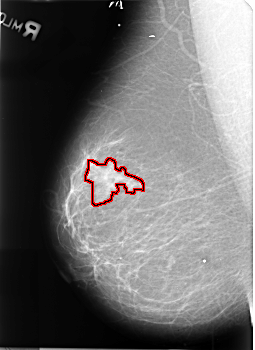

B_3407_1.RIGHT_MLO

FILE: B_3407_1.RIGHT_MLO.OVERLAY

TOTAL_ABNORMALITIES 1

ABNORMALITY 1

LESION_TYPE MASS SHAPE IRREGULAR-ARCHITECTURAL_DISTORTION MARGINS ILL_DEFINED-SPICULATED

ASSESSMENT 4

SUBTLETY 4

PATHOLOGY MALIGNANT

TOTAL_OUTLINES 1

BOUNDARY